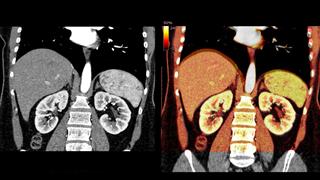

Ο FDA ενέκρινε το Ozempic για τη συμβολή στη μείωση του κινδύνου σοβαρών νεφρικών επιπλοκών σε ανθρώπους  με διαβήτη τύπου 2 και χρόνια νεφρική νόσο.

Η νέα έγκριση στις ΗΠΑ επιτρέπει στους γιατρούς να συνταγογραφούν σεμαγλουτίδη για τη μείωση του κινδύνου νεφρικής ανεπάρκειας, αιμοκάθαρσης και θανάτου από προβλήματα που συνδέονται με την καρδιά σε αυτούς τους υψηλού κινδύνου ασθενείς.

Η απόφαση βασίστηκε σε έρευνα που δείχνει ότι άνθρωποι με διαβήτη 2 και  ΧΝΝ που το λάμβαναν είχαν 24% χαμηλότερο κίνδυνο για επιπλοκές που συνδέονται με τα νεφρά όπως ανάγκη για αιμοκάθαρση ή μεταμόσχευση.

Οι ασθενείς στην έρευνα επίσης είχαν χαμηλότερα ποσοστά νεφρικής έκπτωσης και ήταν λιγότερο πιθανό να πεθάνουν από καρδιακά προβλήματα.

Το Ozempic χρησιμοποιείται κυρίως για τον έλεγχο του σακχάρου αλλά ερευνητές εικάζουν ότι μπορεί ενδεχομένως να μειώνει και τη φλεγμονή στα νεφρά και σε όλο τον οργανισμό.